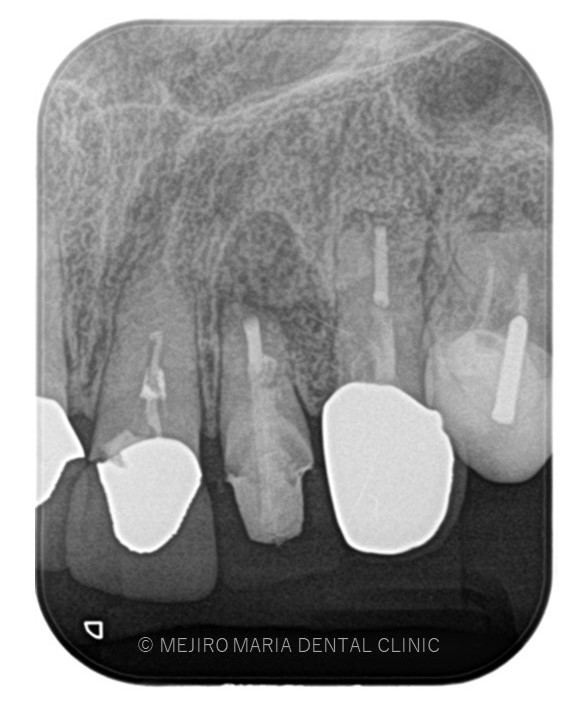

でのリカバリー_歯根端切除術直後のレントゲン画像.jpg)

でのリカバリー_術後3ヶ月後のレントゲン画像.jpg)

レントゲン写真より根尖部の骨は3ヶ月で順調に再生していると考えられます。

また、術前に訴えておられた違和感や腫脹、瘻孔は消失しており、現時点で経過は良好であると判断しています。

引き続き経過観察を継続していきます。